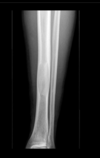

Fratura do platô tibial lateral - Schatzker tipo 2 (traço de fratura + depressão do plato lateral).